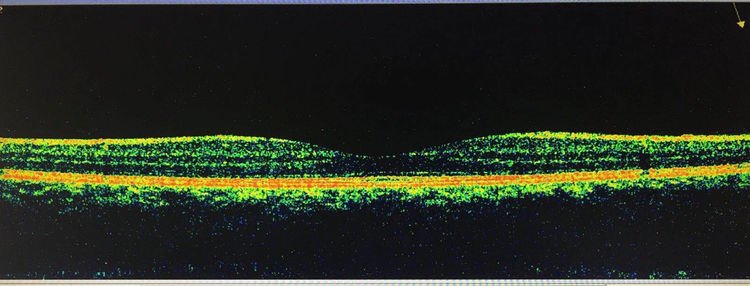

下面是一张正常的视网膜黄斑中心凹的OCT图像,也就是黄斑区的断层扫描,它的中心是一个锥形小凹,能够将物体的反射光线聚焦在小凹上,从而让我们看清楚物体的微细结构,正常情况下它的厚度是250 µm。